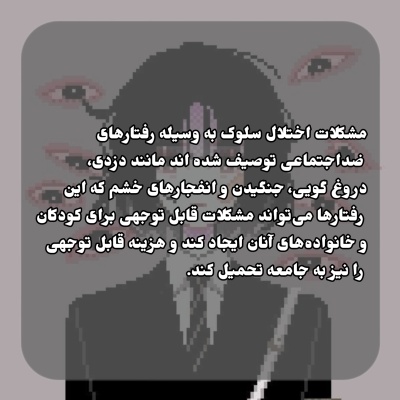

معرفی اختلال سلوک؛ اختلالی در رابطه با رفتار پرخاشگرانه کودکان و نوجوانان.